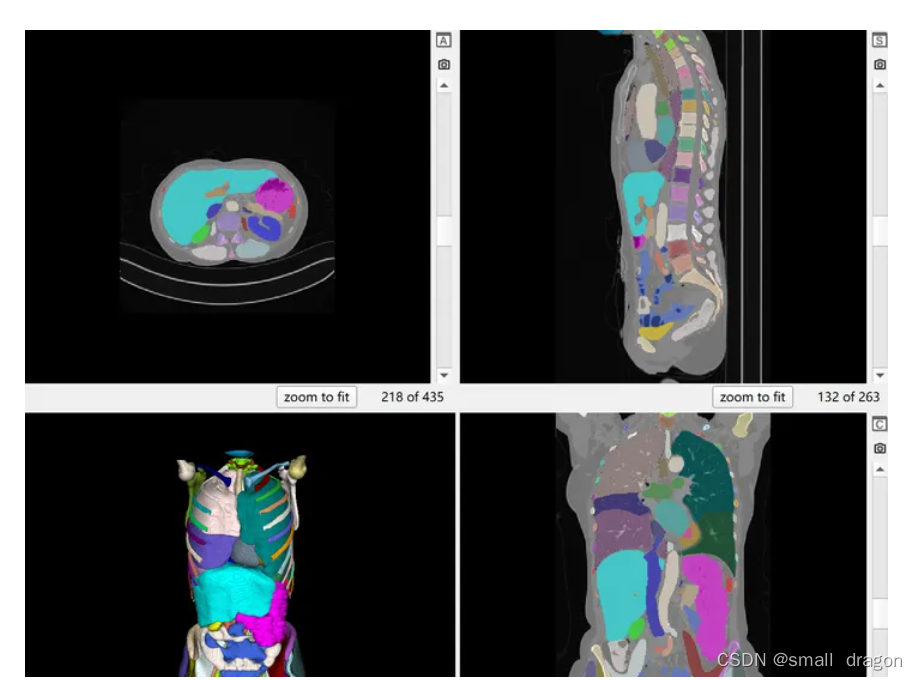

1、TotalSegmentator数据集

是目前三维医学图像分割领域的最大公开数据集,包括 1204 张 CT 图像,覆盖全身的 104 种解剖结构。其中,1082张用于训练,57张用于验证,65张为测试集。与大多数仅聚焦于部分器官且数据量有限的数据集不同,TotalSegmentator 提供了前所未有的数据规模和多样性,更好地适应了临床的多变场景。此数据集不仅覆盖了常见器官,还标注了其他数据集中罕见的结构,为模型研究和优化提供了坚实基础。

可视化